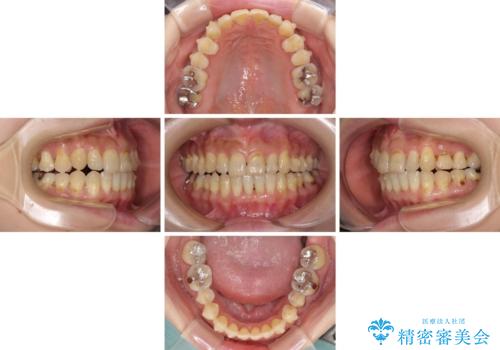

- 歯列不正と、どこで咬んで良いのか分からない咬み合わせを気にして来院された患者様です。

下顎骨は左側にシフトしており、咬み合ったときには奥歯と前歯の一部しか接触していない状態でした。

骨格的な左右差は歯列矯正は改善できないため、上下歯列が全体的に接触することをゴールとしてインビザラインにて矯正治療を行うこととしました。

マウスピース矯正は、奥歯が常にマウスピースを介して咬み合うため、治療過程において前歯のみが接触して奥歯が咬み合わないということが頻発します。

元々奥歯の咬み合わせに問題のある方の場合、治療期間が長期化したり、咬み合わせの改善ができなかったりすることがあります。